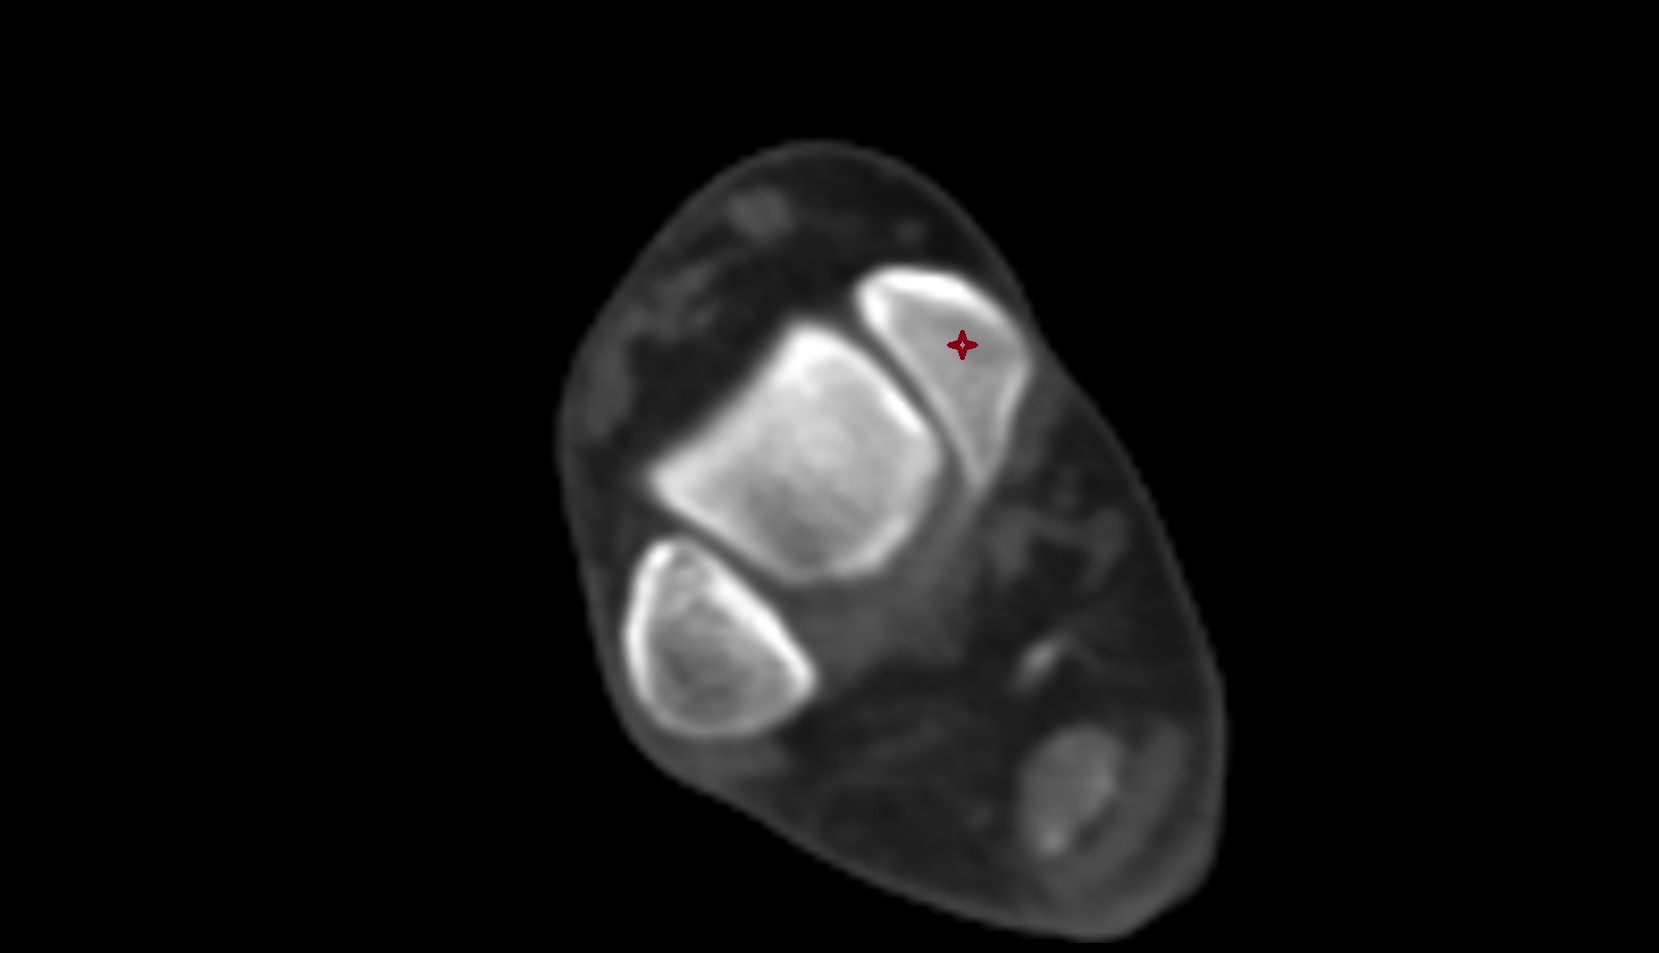

- Knee Joint